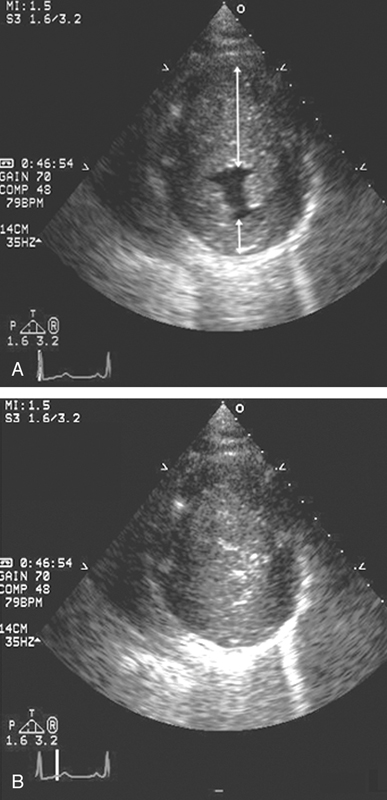

فحوصات تشخيصية لبعض امراض القلب والشرايين التاجية